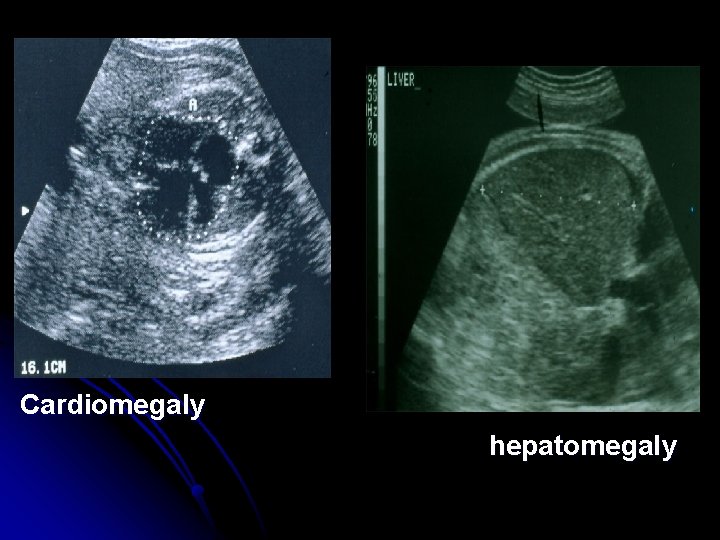

Ultrasonic detection of Rh sensitization -Serial ultrasonic examination for placental size and thickness and hepatic size. -Fetal hydrops diagnosed by; -asictes -pleural effusion -pericrdial effusion -Skin edema

Cardiomegaly hepatomegaly